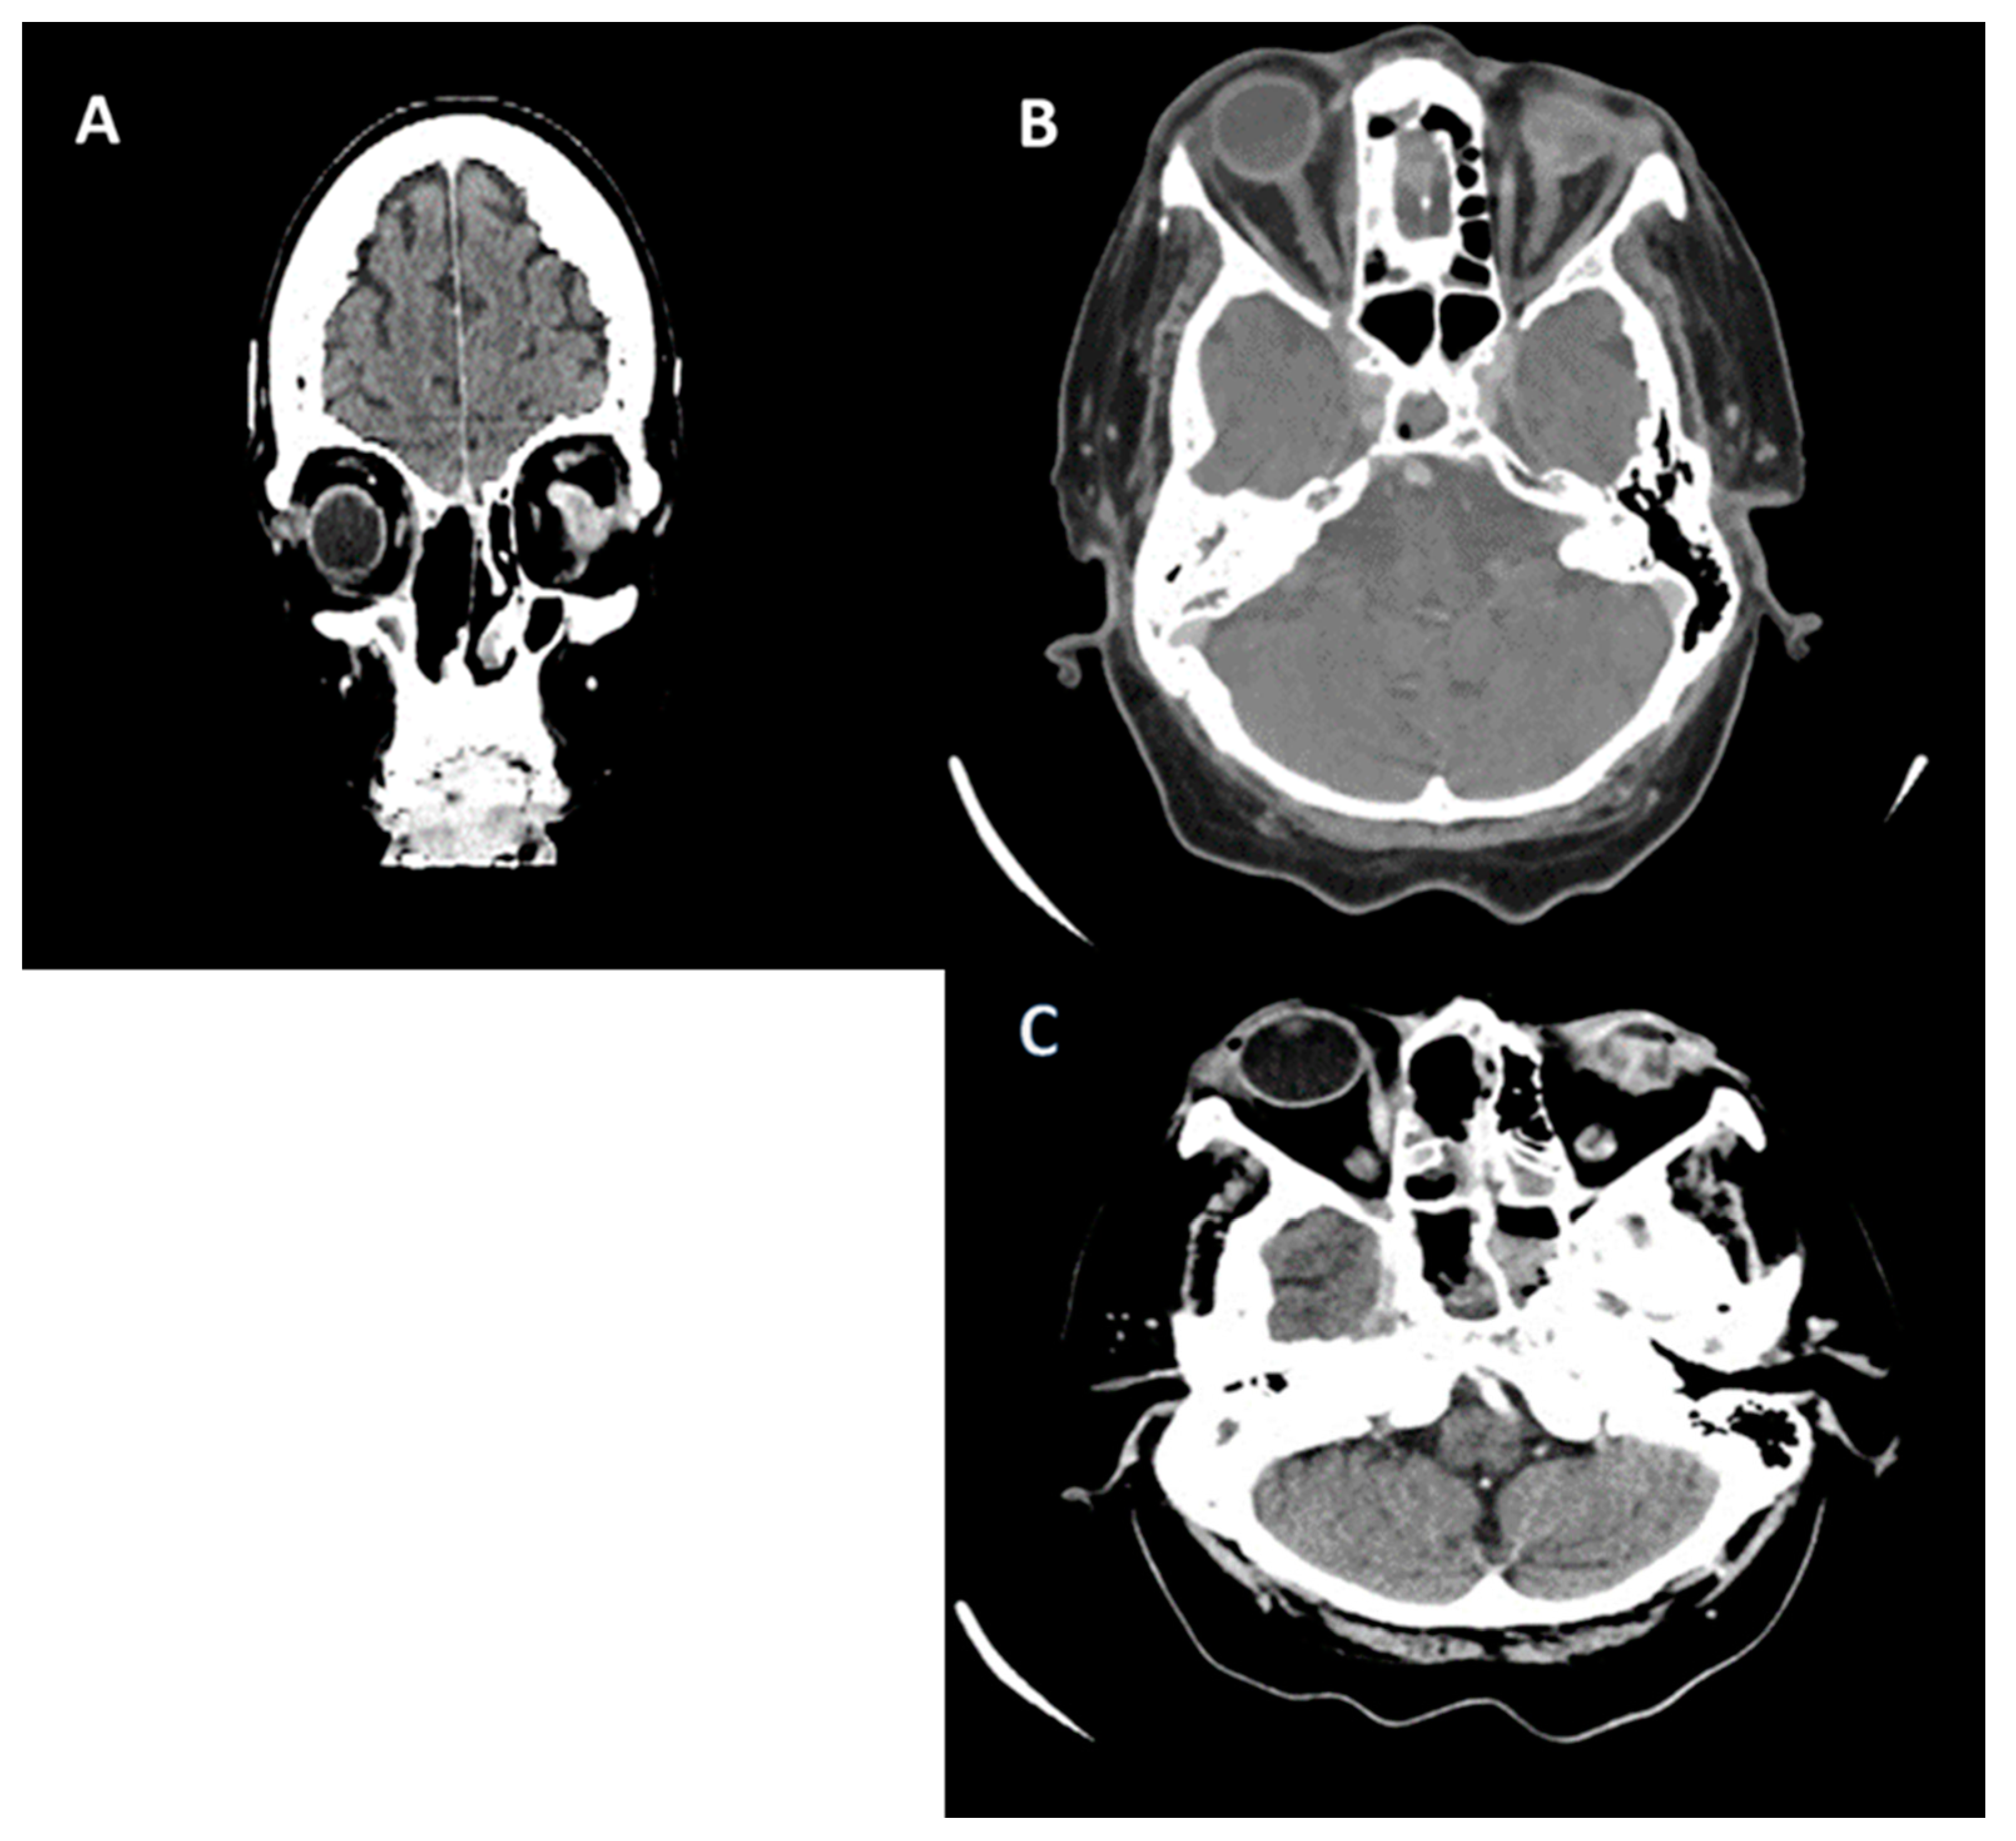

Subsequently, on 30 August 2022, he developed edema in the upper and lower eyelids, diffuse facial edema with Celsian signs, and associated centrofacial vascular necrosis at the level of the nasal pyramid with right orbital extension and the involvement of the right maxillary sinus, accompanied by headache, leading to admission to the Ear Nose Throat (ENT) department, Figure 2. A macroscopic anatomopathological examination revealed multiple necrotic fragments and a microscopic examination showed multiple histological sections represented by necrotic-inflammatory material, with numerous bacterial colonies and fungal filaments, and some branching at a 90-degree angle, consistent with mucormycosis, Figure 3. Cranial CT showed massive destructive infectious processes involving the maxillary sinuses, posterior ethmoid cells, and orbits with involvement of the right eye globes, possibly of mixed fungal and bacterial etiology, Figure 4. Surgical treatment was instituted by performing a total necrectomy of the centrofacial necrotic focus along with antibiotics (amoxicillin-sulbactam, cefoperazone) for 10 days and antifungal therapy with posaconazole (for 9 weeks) due to myelosuppression. Amphotericin B and isavuconazole were not available at that time in the hospital. Postoperative recovery was satisfactory, and subsequently, he was transferred to the hematology service for further specialized treatment.

Figure 4. Cranial CT (scale bar equals 1.25 mm). (A,B) The image of the coronal computed tomography shows thickening of the mucosa and homogeneously walled-off collections with air inclusions, localized in the left sphenoidal sinus, bilateral frontal maxillary sinuses, and ethmoidal cells, post-necrotic bone structure changes with the interruption of the bone cortex, and multiple osteolytic lesions in the bilateral fronto–ethmoido–maxillary regions, as well as in the nasal septum and nasal bones. (C,D) Right eyeball with reduced dimensions and altered structure with a shrunken appearance.